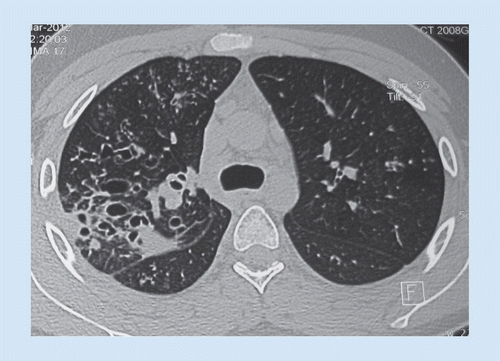

Allergic Bronchopulmonary Aspergillosis is essentially a hypersensitivity reaction to a fungus known as aspergillosis fumigatus. Though common in environment, this fungus does not cause allergic reaction in all the individuals who come in contact with it. The allergic reaction affects the lungs. There is a strong association between Allergic Bronchopulmonary Aspergillosis with cystic fibrosis and asthma. The patient with Allergic Bronchopulmonary Aspergillosis presents with: - Productive cough with brown or blood-stained sputum - Malaise - Weakness - Fever The diagnosis of Allergic Bronchopulmonary Aspergillosis is made on the basis of history, clinical picture, and investigations such as hematology profile and radiology. In asthmatic patients, it is imperative to continue the medication in order to maintain the airways to facilitate the expulsion of fungus from lungs. Oral itraconazole is also given, however, its use is controversial. Reference: https://www.aaaai.org/Conditions-Treatments/related-conditions/allergic-bronchopulmonary-aspergillosis Image via: https://www.futuremedicine.com/doi/10.2217/fmb.14.74